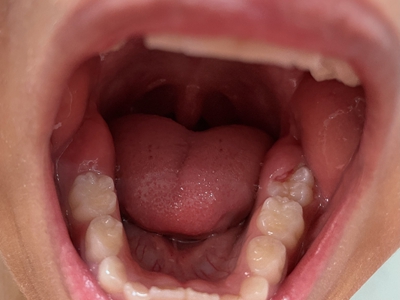

牙龈炎是发生于牙龈组织的炎症,患者可出现牙龈出血伴肿胀、发红、正常形态改变和偶尔不适等症状。本病主要由口腔卫生状况差导致,包括口腔不洁、牙菌斑等,诊断依据临床检查,治疗包括专业牙齿清洁和加强家庭口腔卫生。

牙龈炎可先引起牙齿与牙龈之间的沟(龈沟)加深,然后牙龈充血,炎症围绕一个或多个牙齿,伴牙龈乳头肿胀和易出血。一般无痛,可自行消退,也可维持轻度炎症数年。